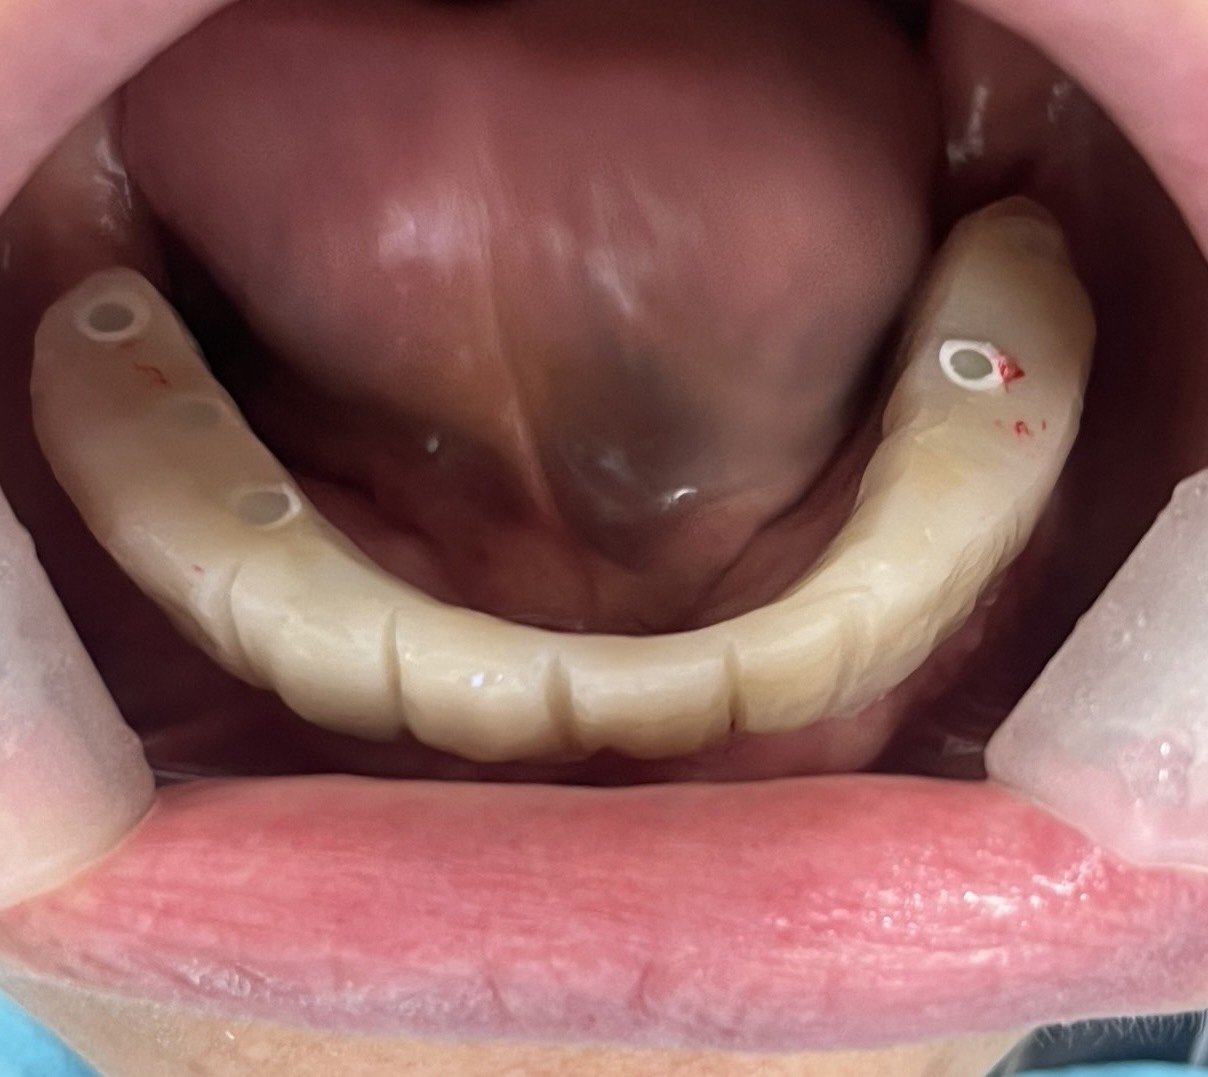

一位患者特地從外州飛到拉斯維加斯,評估後當天決定進行全口植牙。整個療程不到兩小時,即拔即植即固定臨時牙。

手術當天完成全口掃描,四個月後更換為最終固定假牙。這段期間,患者維持良好的生活品質,醫師也能安心照護,不用每天提心吊膽、接不完病患來電。

不需要全身麻醉,或者是舒眠麻醉的情況之下,就完成與自然牙排列相仿全口重建。不用擔心歪斜長長的植體打到顴骨或眼睛。